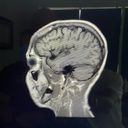

I’m out of work with a concussion and head injury. I’m getting good treatment but it takes a long time and I’m the bread winner for my family. Anything will help until I’m back to working full time. I’m a single mom of a wonderful teen and a new puppy mom as well. I’m a gardener and artist and living paycheck to paycheck.